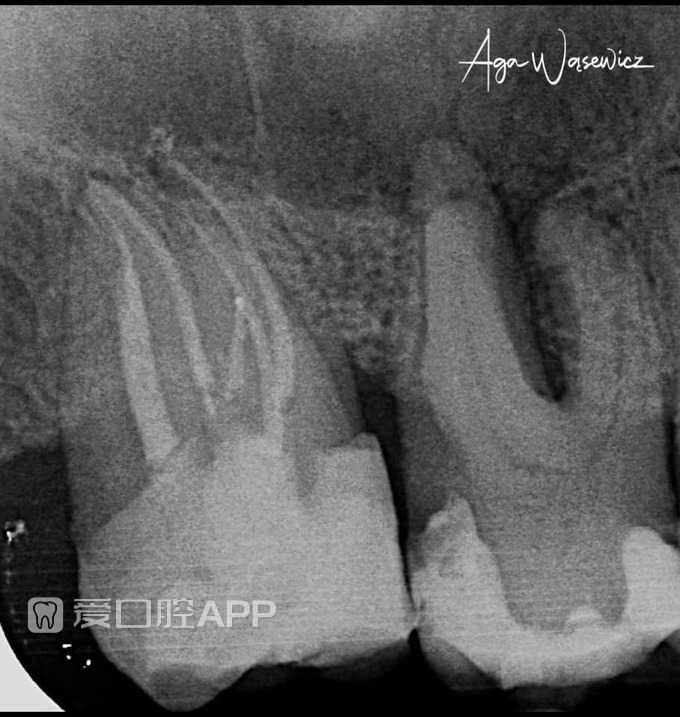

看个根充 —— 5根管的上颌第二磨牙

by Aga Wąsewicz